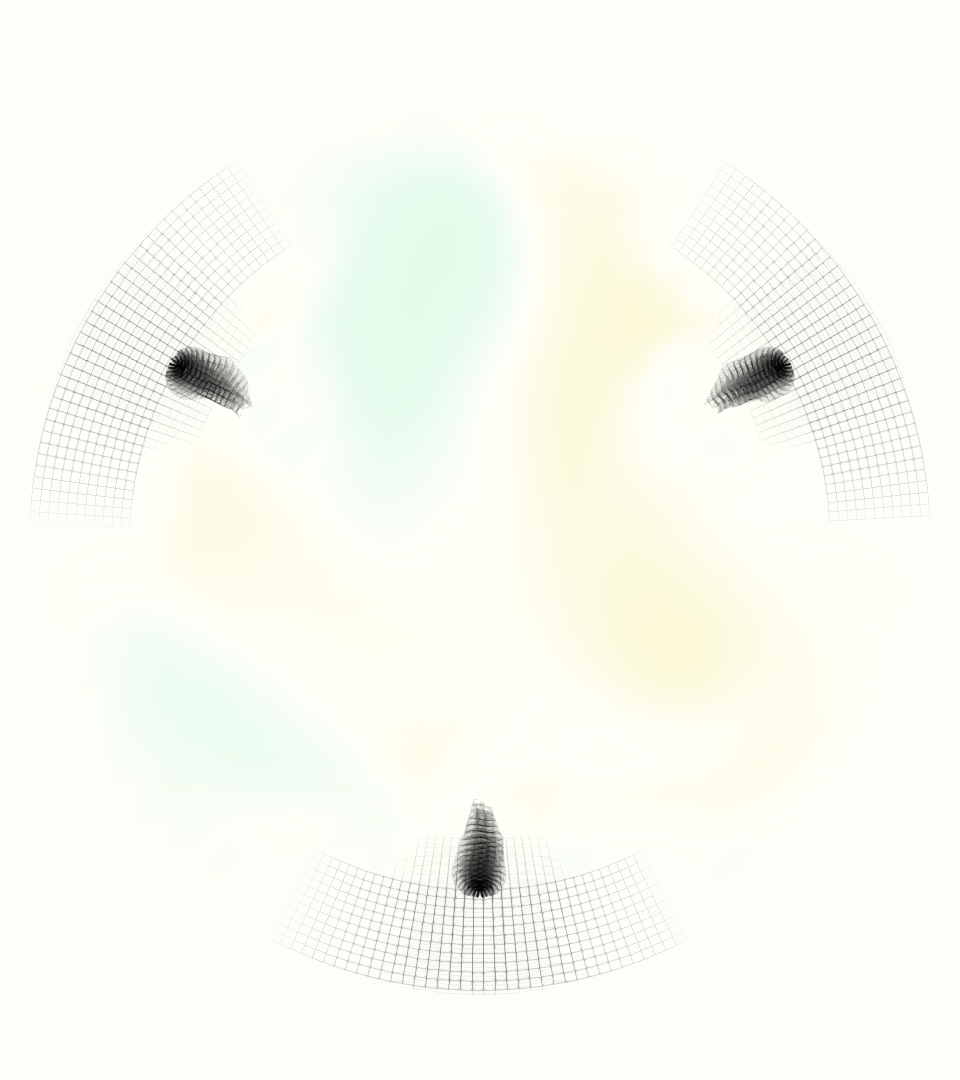

The emergent hemodynamics showed excellent qualitative agreement with experiments. Slice views of the axial component of fluid velocity ( component) in the sagittal plane that cuts through the center of the vessel, parallel to the flow direction, are shown in Figure 5. The flow in both the simulation and the experiment began to accelerate at the same time, with a jet forming through the open valve leaflets. The velocity, angle, and shape of the jet agreed well between the two cases during systole. The simulation captured the slight upward angle of the jet, which was not fully centered in the vessel. It also matched the location where the jet impacts the wall and the slower speed of the jet as it turns with the MPA downstream. As the flow decelerated, the fluid along the interior curve of the vessel reversed first while forward flow persisted where the jet was strongest, as seen in both the simulation and experimental results.

In both the experiment and the simulation, a separation region of reverse flow developed along the interior curve of the vessel under the core jet through the valve. The reverse flow began to develop at the same time in the cardiac cycle and grows throughout systole. The simulation lacked reversed flow in the entire region where reversed flow was present in the experiment, but this region developed some flow separation and had much slower flow than elsewhere in the vessel. Thus, the simulation captured that this is a distinct region from the core jet through the valve opening. There was a smaller amount of slower and slightly reversed flow along the outer curve of the vessel, close to the valve annulus and scaffold support. This region was well-matched between the experiment and the simulation.

Slice views of the (axial) component of fluid velocity in the axial plane, orthogonal to the flow direction, show that the simulation replicated the development of the jet over the cardiac cycle. At each phase, the simulation matched the forward speed of the core of the jet and the locations of reverse flow back towards the valve annulus. While there are some differences in the shape of the jet at certain phases and locations, the simulation clearly produced the general dynamics of the cardiac cycle that are seen in the experiment.

At = 0, the axial slice directly at the valve annulus shown in columns 1 and 2 in Figure 6, there was excellent agreement between the simulation and experiment over the cardiac cycle in the speed and shape of the jet through the valve. In both cases, the axial velocity increased as the flow accelerated during systole and the valve leaflets opened, then decreased during diastole with slight negative velocity before the valve leaflets were fully closed. The forward flow through the valve annulus did not form a full circle, but rather developed a triangular shape with a point of the triangle forming along the interior curve of the vessel, at the bottom of the axial slices. At = 0, the points of this triangular jet shape aligned with the commissures of the valve. This shape persisted during peak systole and was well-matched by the simulation.

The axial slice = 0.625 cm, shown in columns 3 and 4 in Figure 6, cut through the support scaffolding of the valve and the leaflets when they are open. In the experimental data, the shape of the jet changed as it moved downstream. A triangular shape occurred, but the points were then aligned with the middle of each open leaflet as opposed to the commissures. Those points were also more rounded than they were at = 0. The peak velocity of the jet was faster at = 0.625 cm than at = 0, as the flow accelerated through the open valve leaflets. The simulation produced these features at = 0.625 cm. The triangular shape of the jet shifted similarly, and its speed increased compared to the upstream slice. As the flow decelerated into diastole, the jet shape remained roughly triangular but diminished in intensity before disappearing after valve closure.

The jet continued to develop at = 1.25 cm, an axial slice immediately downstream of the valve scaffolding and open leaflets, shown in columns 5 and 6 in Figure 6. In the experimental data, the points of the triangular jet shape extended further towards the vessel wall. In addition, regions of reversed flow developed in the locations downstream of the commissures, resulting in curved sides to the shape of the jet. Each tip of the jet was unique, due to variations in the individual leaflets in the physical bioprosthetic valve. These variations are apparent in the velocity fields, possibly because the jet edges are similar enough cycle to cycle that irregularities are still being captured even with phase averaging. Further discussion of these features can be found in Schiavone et al. [39], which showed that the jet tip shapes occurred in different pulmonary anatomies, demonstrating that they were likely due to inherent properties of each leaflet. The leaflets in the mathematical model of the valve are identical, so these nuances in leaflet variation could not be replicated. The simulation did capture some of the extension of the tips of the jet, as they were closer to vessel wall at slice = 1.25 cm than = 0.625 cm. The curves in the triangular sides of the jet were also present in the simulation, though they were less pronounced than the experimental data. At both = 0.625 cm and = 1.25 cm, the jet shape in the simulation was smoother than the jet in experiment. It is possible that the free edges of the leaflets in the mathematical model are not fully replicating the behavior of the physical leaflets of the bioprosthetic valve, in particular the amplitude or frequency of leaflet flutter, leading to the variations seen in the jet shape at = 1.25 cm downstream of the leaflet edges. The simulation, however, does capture the key features of the triangular shape and speed of the jet. Overall, qualitative comparisons demonstrated that the simulation reproduced key features of the flow during systole and diastole.